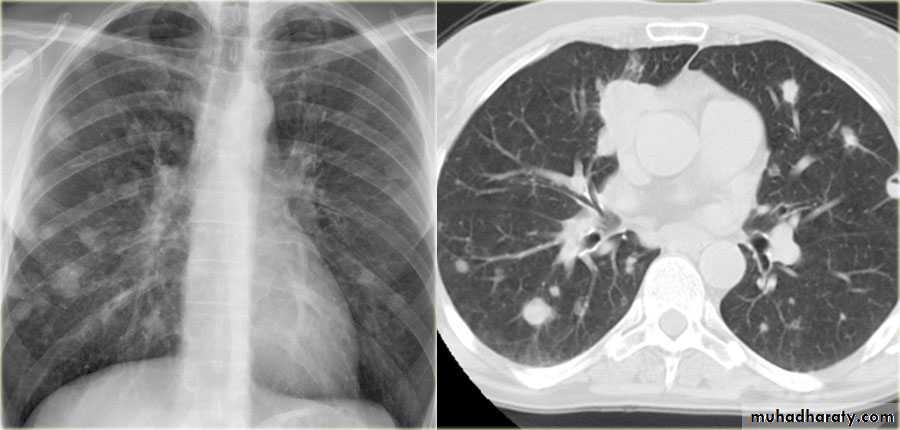

Patient with fever, rigor and dyspnea